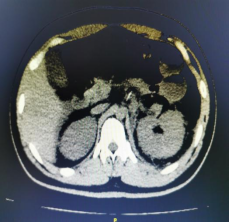

小志(化名)是因左腹部疼痛近半月,当地医院彩超左肾门占位而就医,入院后行双肾核磁,结果显示左肾门占位,大小约为5.8cmX5.0cmX6.2cm,肾盂输尿管膀胱64层螺旋CT三维成像结果显示左肾边缘毛躁,左肾周筋膜增厚,左肾周可见迂回血管影。该肿瘤不仅体积大,血管丰富,位置还“刁钻”,其与肾动脉、肾静脉、输尿管关系密切,实施保留肾脏肿瘤切除术难度极大,风险也随之加倍。ac米兰官网中文网站一院群力泌尿外科团队决定勇闯技术难关,迎难而上,挑战高难度保肾肿瘤切除术。

术前肿瘤3D可视成像 术后肿瘤切除后肾脏血运良好